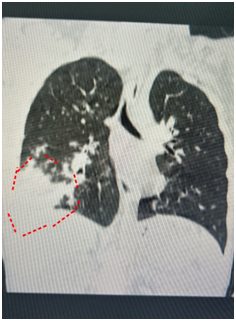

悠悠退烧后却一直咳嗽,越咳越厉害,这才来到医院。经过胸部CT检查,他的右肺已经白掉了一大块。之后的化验结果证实,悠悠患上了支原体肺炎 ,马上被收治入院。

郑绪阳说,近年来,不典型症状的肺炎越来越多,很多肺炎患儿血象不高,咳嗽也不厉害,发现久咳不愈出现气喘才来检查,结果肺部CT一检查,发现肺已经白掉了一大块。